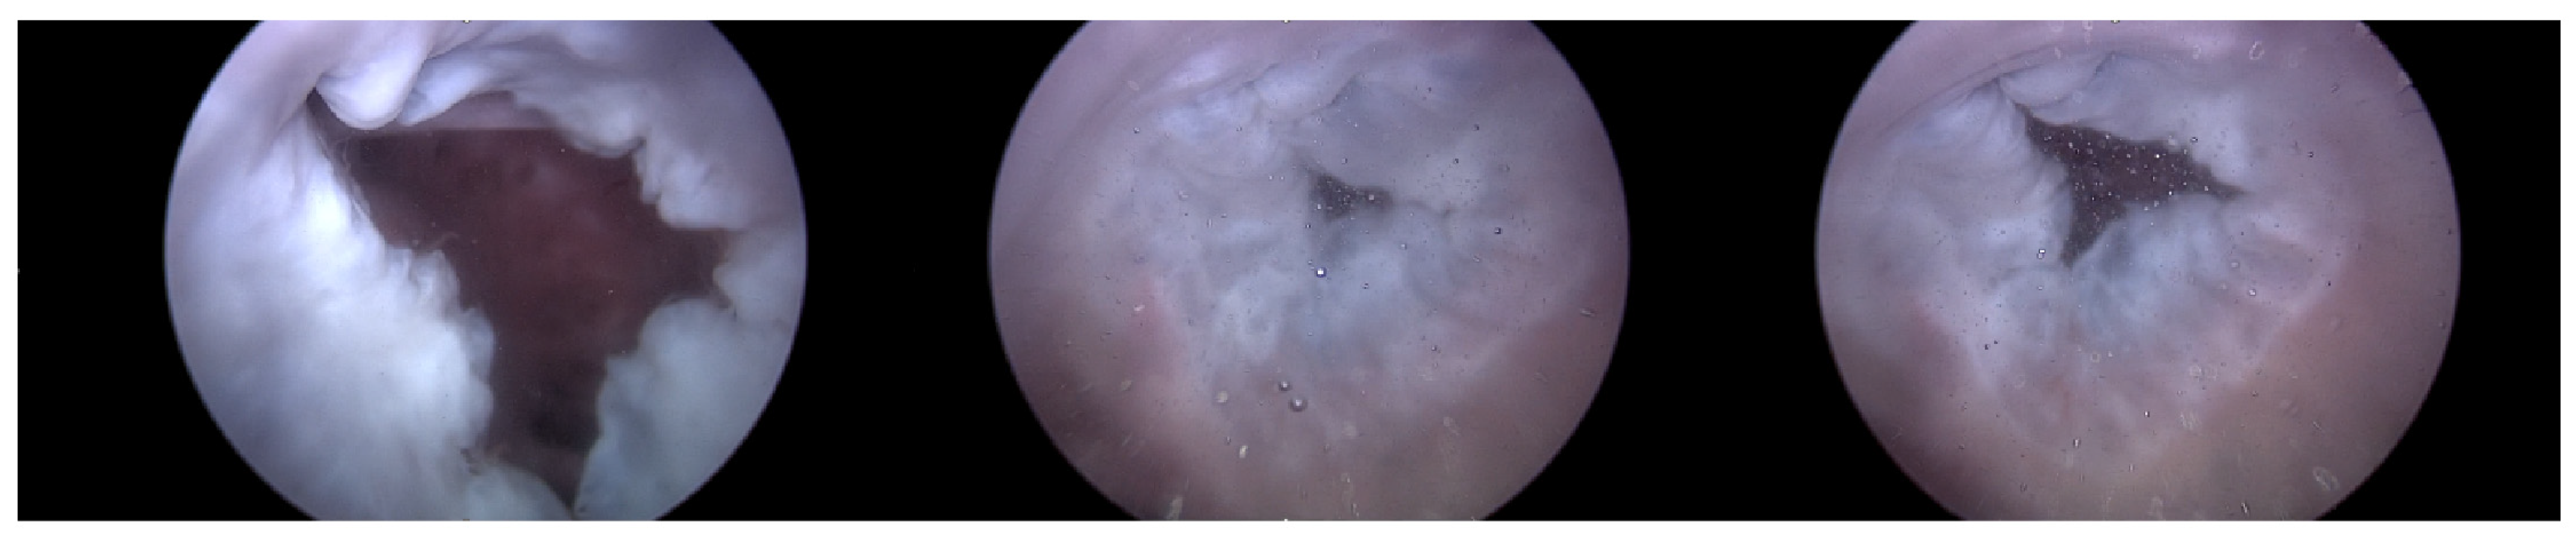

The Pivot-TR (Figure 1 and Figure 2), developed by Tau-PNU Medical Co. in Yangsan, Republic of Korea, is an innovative device designed to mitigate TR. It comprises a pivot axis formed from a nitinol wire with components named “the elephant nose” and “the spiral anchor” and a 3D leaflet enveloped in an expanded polytetrafluoroethylene (ePTFE) coating. The spiral anchor is equipped with a hook at the proximal end to allow for the retrieval of the snare at a later time. Positioned at the TV’s intersection point, the device allows for real-time adjustments of its wire tension, enabling clinicians to optimize the angle and position of the pivot axis based on observed blood leakage, thereby reducing TR’s hemodynamic impact [9]. The diameter of the anchor in this study was 35 mm.

Figure 2. The experimental setup and how to use the Pivot-TR device in a heart [9].

Figure 15. Endoscopic image of Heart 2 with Pivot-TR (valve open, normal valve closed).